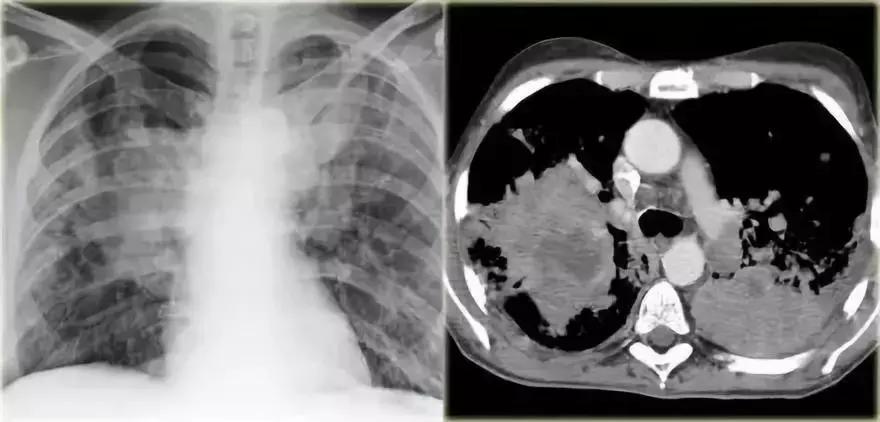

支气管肺泡癌弥漫性实变

➢ 胸部X线显示左肺出现“白肺”弥漫性实变,伴有空气-支气管征

➢ 患者是进行性实变的慢性疾病

➢ 患者左肺持续实变,最终扩散到右肺

最终诊断:支气管肺泡癌

图12 支气管肺泡癌弥漫性实变